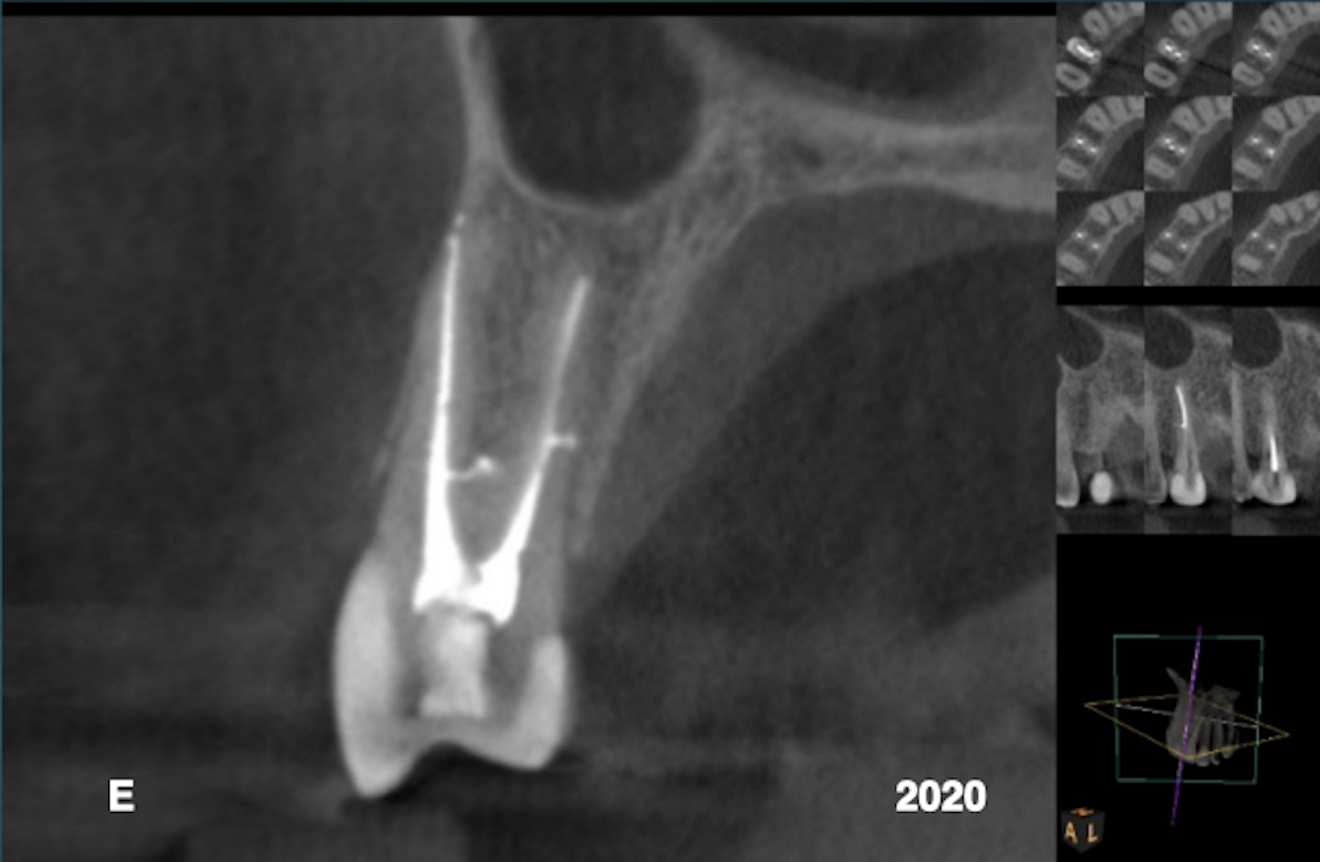

The patient provided a periapical radiograph showing a mesio-proximal periradicular radiolucency associated with tooth #15 (Fig. 1). The sagittal slice of the CBCT volume (Carestream CS 9000, Carestream Dental) showed the extent of the lesion (Fig. 2). In the previous root canal therapy, only the buccal canal had been detected and treated. The axial slice showed an untreated palatal canal (Fig. 3). A fibre post placed in the buccal canal had been used to retain the core. The patient was advised of the misdirected anchoring pin extending into the periodontal ligament. With the patient’s consent, it was decided to selectively treat the palatal canal.

After an interim six-week period of calcium hydroxide therapy (UltraCal XS, Ultradent; Figs. 4 & 5),6 the root canal space was obturated using a warm vertical condensation technique.7 The obturation material was expressed into a lateral branching portal of exit (Fig. 6). The four-year follow-up showed resolution of the lateral lesion (Figs. 7–9). The initial presumption of a fractured root was proven false, suggesting that diagnosing conditions based on insufficient data acquisition is unreliable. The use of CBCT is an imperative in endodontic procedures of any kind provided ALARA (as low as reasonably achievable) principles regarding radiation dose are followed.

Case 1—Fig. 1: An area of periradicular rarefaction was evident along the mesio-proximal aspect of tooth #15. Previous root canal therapy and a pin-retained post and core supporting a zirconia crown were noted. Fig. 2: The sagittal slice of the CBCT volume showed the lateral lesion extending to the alveolar crest. Fig. 3: The axial slice of the CBCT volume showed the extent of the rarefaction adjacent to the mesial aspect of the root and the presence of an untreated palatal canal. Fig. 4: Selective treatment of the palatal canal was performed. Calcium hydroxide was inserted in the canal space. Fig. 5: The extrusion of the interim calcium hydroxide medicament through the sulcular area of tooth #15 was evident. Fig. 6: A lateral branch of the root canal space containing the obturation material exited into the interface of the middle and apical thirds of the root. Fig. 7: A periapical radiograph taken four years after treatment showed osseous regeneration and the reformation of the periodontal ligament. Fig. 8: The coronal slice of the CBCT volume showed the pre-op periradicular radiolucency. Fig. 9: The coronal slice of the CBCT volume taken four years after treatment showed the resolution of the periradicular radiolucency.